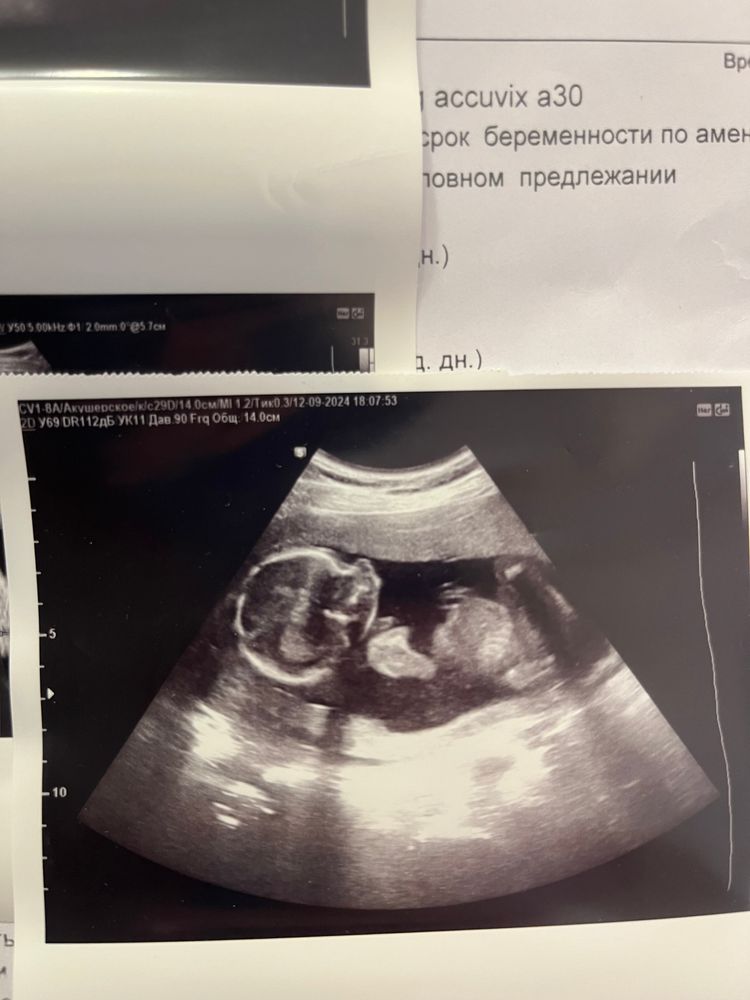

Шла 18неделя ❤️

Шла 18 неделя,дочь сосала палец на узи,обещала врачу ее покормить дома 😅край плаценты так же перекрывает внутренний зев..что ж,будем ждать поднятие 🤷🏻♀️